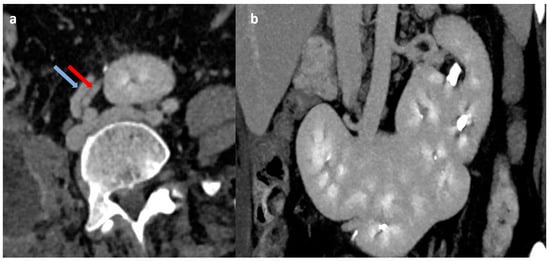

Figure 1.

Contrast-enhanced CT abdomen images (a) in axial plane showing the vascular supply of transversely oriented supernumerary kidney unit from right common iliac artery (red arrow) and vein (blue arrow); (b) in coronal plane showing triple fused supernumerary kidneys.

A female in her mid-40s presented to the emergency department with acute onset umbilical pain associated with vomiting. There was no flank pain, hematuria, dysuria, or fever. An ultrasound of the abdomen and pelvis was performed, which showed an empty right renal fossa and fused, conglomerated reniform-shaped structure in the midline at the umbilical region with vascularity noted on Doppler imaging. The patient was further advised on a cross-sectional study for better characterization. A contrast-enhanced computed tomography (CT) study of the abdomen with CT urography was performed, which showed empty right renal fossa and ectopic right kidney in the midline, which was fused with another kidney unit, which was further fused with the lower pole of the left kidney. In contrast sequences, the supernumerary kidney was receiving blood supply from the right common iliac artery and draining through the right common iliac vein, and both right and left kidneys had a normal vascular supply from the aorta and inferior vena cava (Figure 1). On delayed images, both the right ectopic kidney and left kidney showed a bifid pelvicalyceal system, and the supernumerary kidney showed a single pelvicalyceal system, with a total of five pelvicalyceal systems present in our patient (Figure 2). The patient was managed conservatively and became asymptomatic after 2 days.